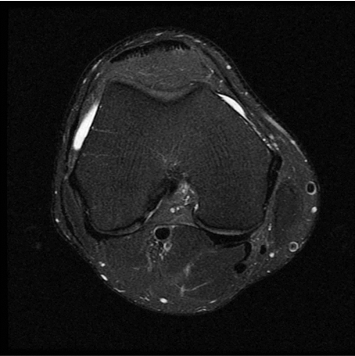

Conventional

384 x 256 (4 NEX)

3:00 minIAI (Innovative AI)

384 x 256 (2 NEX)

1:29 minscan time reduced up to 50%